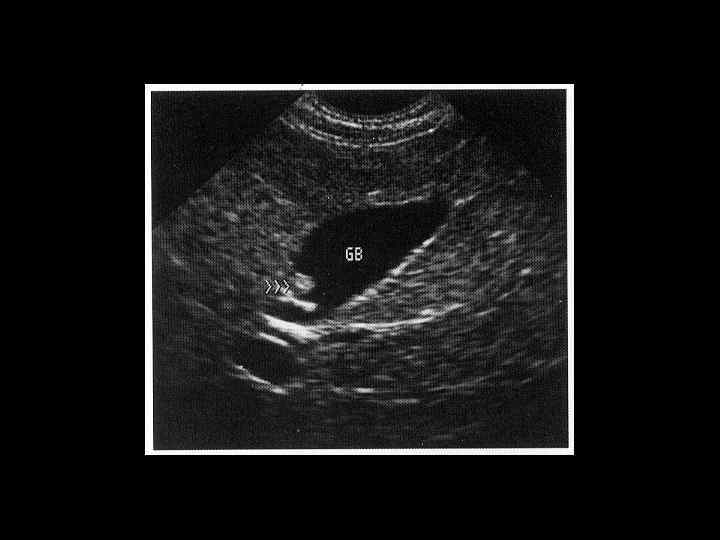

АКТУАЛЬНЫЕ ВОПРОСЫ РЕНТГЕНОЛОГИИ ЛУЧЕВАЯ ДИАГНОСТИКА ЗАБОЛЕВАНИЙ ЖЕЛЧЕВЫДЕЛИТЕЛЬНОЙ СИСТЕМЫ Желчекаменная болезнь УЗ семиотика